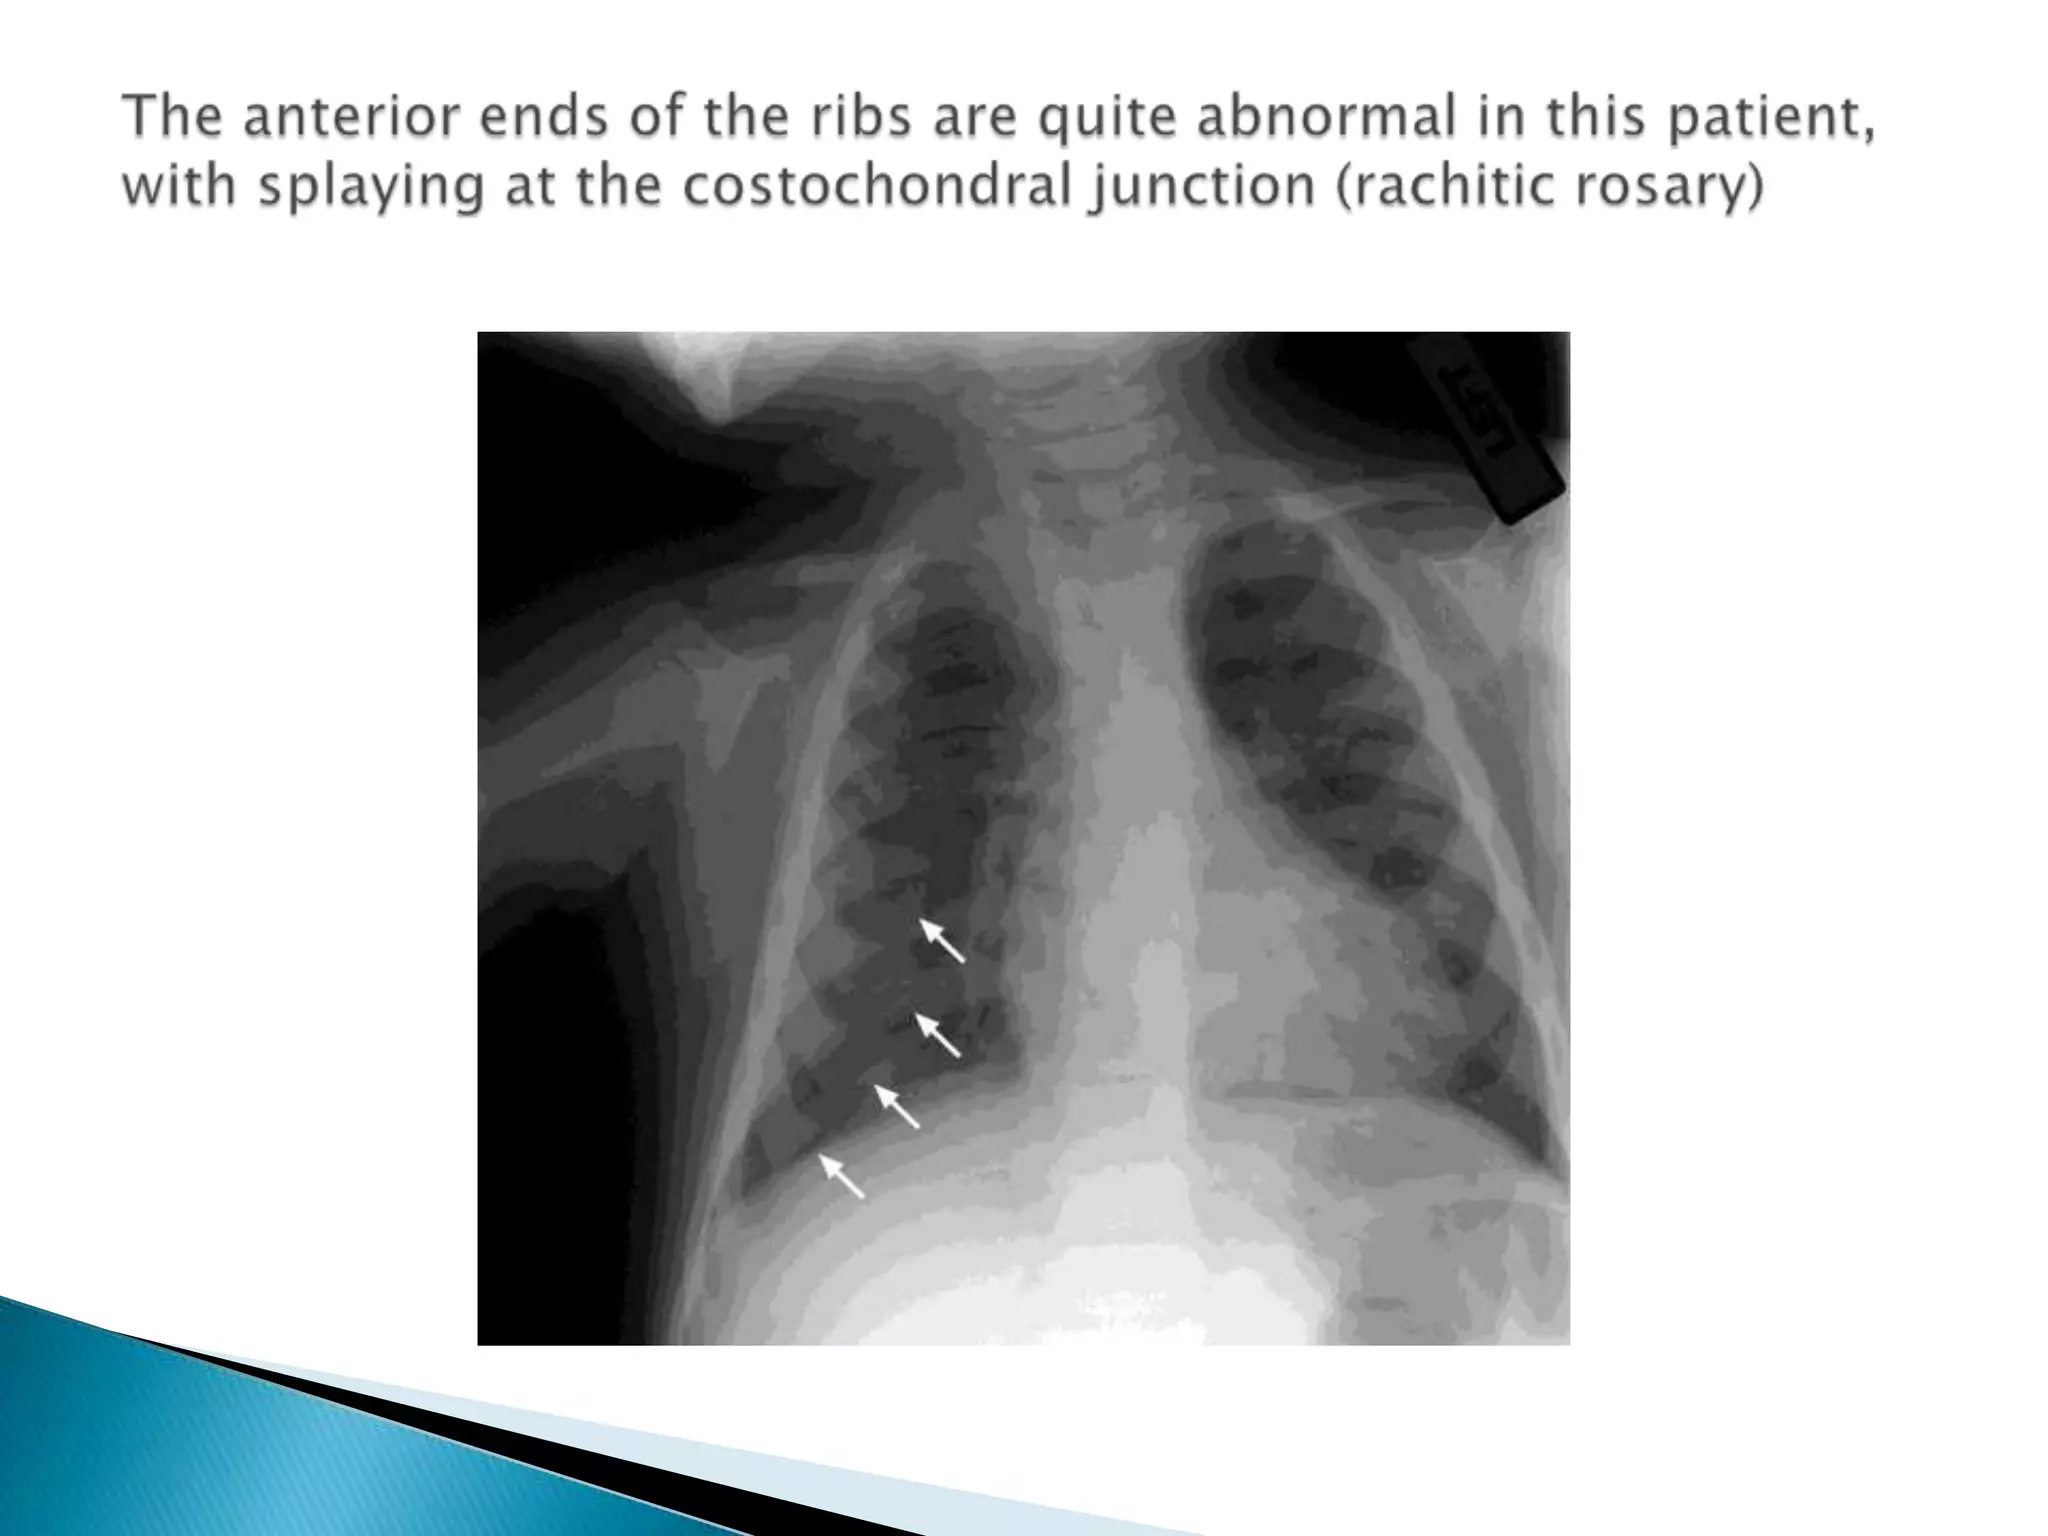

The anterior ends of the ribs are quite abnormal in this patient, with splaying at the costochondral junction (rachitic rosary)

The anterior endsof the ribs are quite abnormal in this patient, with splaying at the costochondral junction (rachitic rosary)